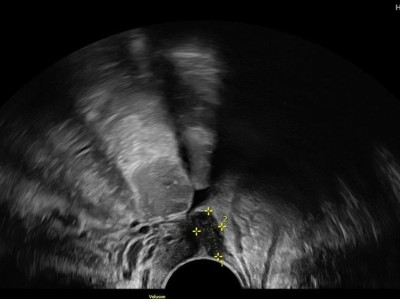

Endometriose und Kinderwunsch – wann operieren, wann nicht?

Eine Operation kann auch bei Endometriose-Patientinnen mit unerfülltem Kinderwunsch der richtige therapeutische Schritt sein. Allerdings ist der optimale Zeitpunkt vom Stand der Familienplanung, Lebensalter und der bisherigen Vorgeschichte abhängig. Rein diagnostische Operationen sind obsolet und sollten idealerweise vermieden werden.

Operative Konzepte für die Endometriose-Therapie

Die operative Therapie der Endometriose reicht von der Resektion oberflächlicher peritonealer Herde bis zur interdisziplinären Operation mit partiellen Organresektionen an Darm, Blase, Urogenitaltrakt und Zwerchfell. Die Radikalität sollte der Patientin und ihren Symptomen angepasst werden. Diese Übersicht fasst die aktuellen Konzepte zusammen.